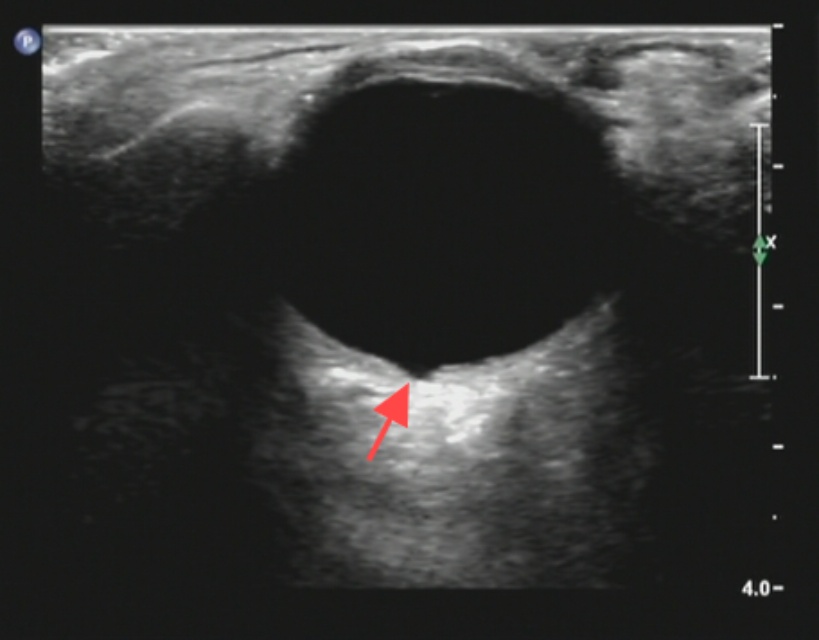

眼部超声多普勒提示:右眼眼球后内壁视乳头颞侧局部回声不均匀,范围约7 mm,内可见一处凹陷,较大范围约1.3 mm × 4.0 mm (见图6);左眼未见明显异常。

Figure 6. The red arrow indicates the depressed area on the temporal side of the optic disc on the posterior inner wall of the right eyeball

6. 红色箭头所指为右眼眼球后内壁视乳头颞侧凹陷部位